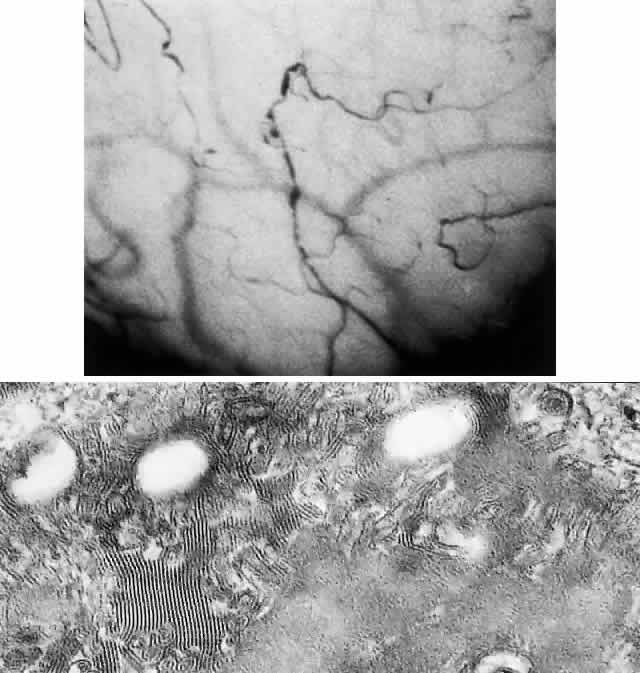

There are many factors that may predispose to lipid deposition in the cornea, but the most common causes are herpes simplex and herpes zoster disciform keratitis. Lipids also may be deposited in the corneal tissues. In the presence of inflammation, vascularization, injury, and corneal edema, the limbal vessels are regarded as the chief source of entry of lipid into the cornea (Fig. 14).115 The deposits appear as dense, yellow-white infiltrates. Cholesterol has been found to be the lipid of note in the case of lipid keratopathy without high blood lipids.151

Fig. 14. Secondary lipid keratopathy after herpes zoster keratitis.

MANAGEMENT. Initial treatment involves controlling the primary inflammatory disease. Argon laser treatment to occlude feeder vessels that have been identified by fluorescein angiography has reportedly been successful in reducing the extent of lipid keratopathy in 62% of cases and its density in 49%.152 Visual acuity was improved in 48% of cases. The use of an Abraham laser lens is important to prevent extensive iris atrophy.153 Complications of corneal argon laser photocoagulation in the treatment of corneal stromal vascularization and secondary lipid keratopathy include iris atrophy, intracorneal hemorrhage, and crystalline deposits.154 Currently, argon laser is seldom used to treat keratopathies.